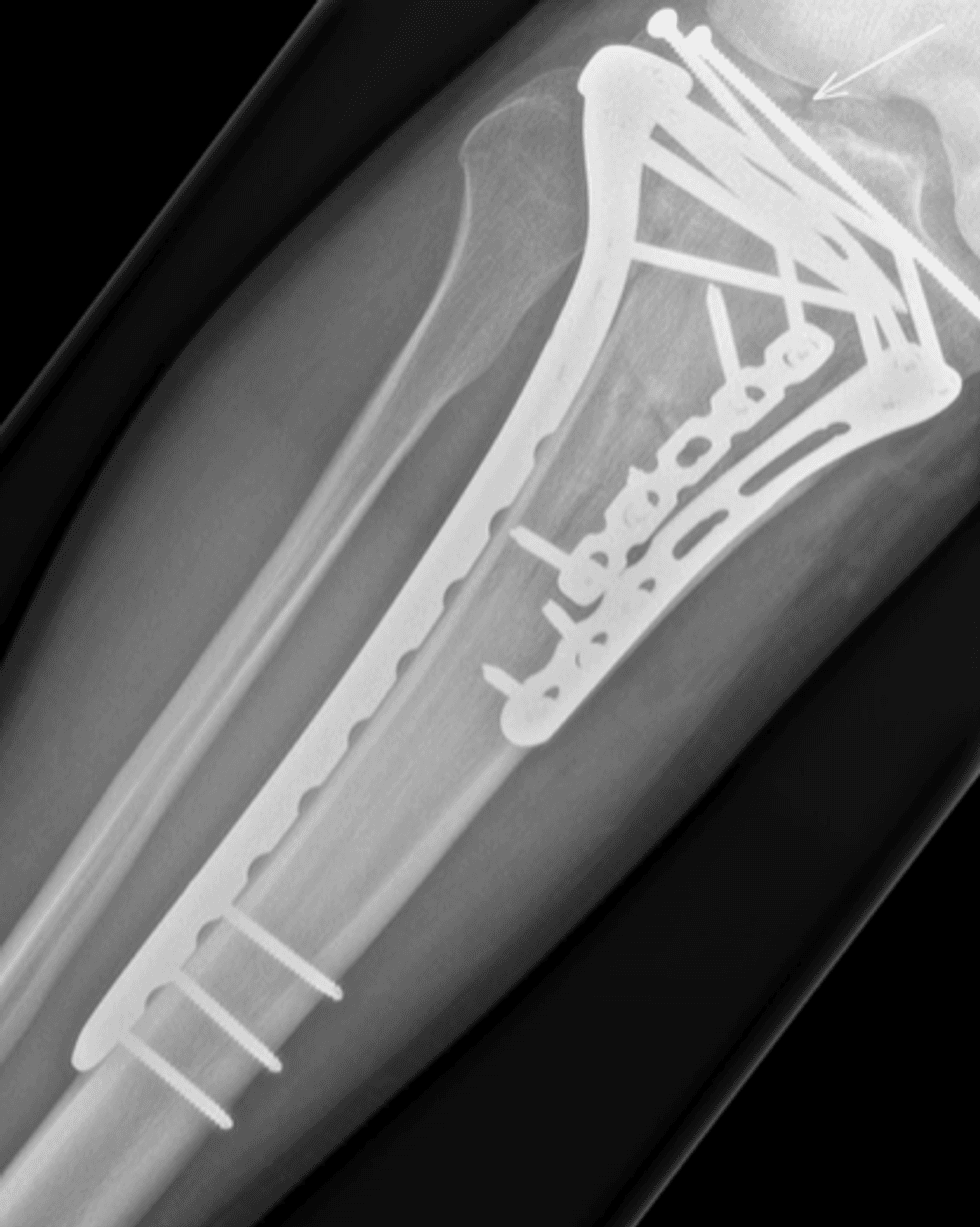

The Edinburgh-born Olympic legend, 49, sustained multiple fractures to his lower right leg and knee during a mountain biking incident in early November, which required emergency surgery in a major trauma ward, where surgeons inserted metal rods and screws into his leg.

Sir Chris Hoy sustained multiple fractures to his lower right leg and knee during a mountain biking incident